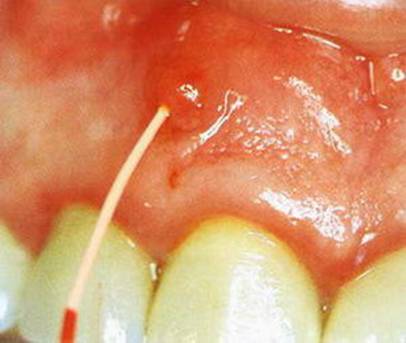

- периодически или постоянно возникающие образования на деснах.

Иногда на деснах вблизи зубов появляются, напоминающие вид прыщей, новообразования. В стоматологии эти образования называются свищевыми ходами. Эти образования сами по себе могут появляться и исчезать, меняться в размерах. Такое состояние наиболее часто обнаруживаются вблизи зуба, в котором омертвел нерв, т.е. заболевание проходит бессимптомно. По этим свищевым ходам происходит отток гноя из инфицированного зуба, что и приводит к появлению неприятного вкуса во рту;